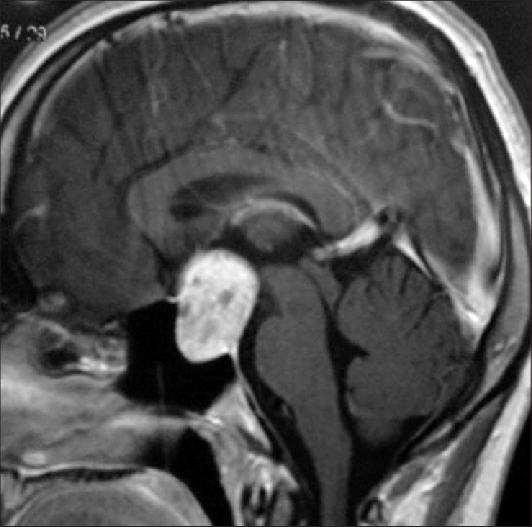

Contoh Tumor kiasma yang menyebabkan atrofi optik kedua mata.

5. Kompresi : Tumor kepala dapat menyebabkan kerusakan saraf optik.

• Pencitraan otak (MRI/CT scan): Jika dicurigai adanya kompresi saraf optik akibat tumor atau kelainan struktural lainnya.